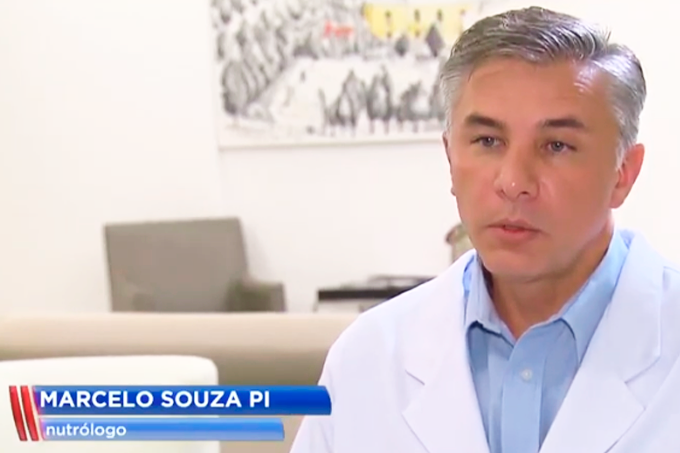

Os termômetros despencaram em várias cidades brasileiras e a primeira consequência é vista nos hospitais, com emergências lotadas por pacientes com gripe, resfriado, pneumonia, entre outras doenças. Para fugir desses problemas, uma alimentação adequada é essencial. A equipe do Jornal da Record conversou com o nutrólogo do Hospital Moriah, Dr. Marcelo Souza Pi, sobre o assunto. Confira!